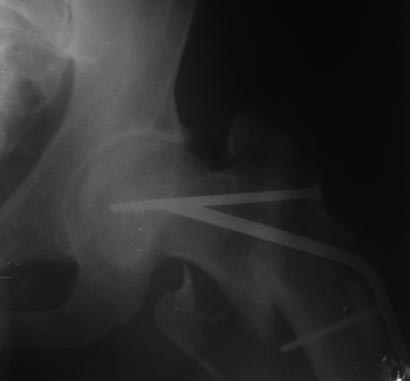

Уважаемые коллеги! На консультацию пришел больной 44-х лет (снимки 1 и 2): упал на улице 26.11.2012г., оперирован в одном из лечебных учреждений 26.11.2012.

Сделали контрольные рентгенограммы и КТ. Хотели-бы обсудить варианты оперативного лечения: DHS или БИОС?